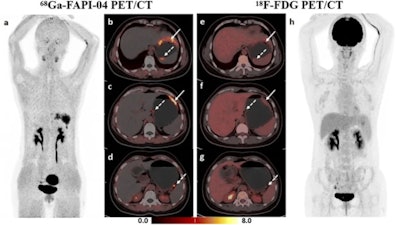

The authors reported that Ga-68 FAPI-04 PET/CT detected more primary lesions (90.3% vs. 77.4%, p = 0.008) and peritoneal metastases (91.7% vs. 41.7%, p = 0.031) and demonstrated higher SUVmax and TBR values (p < 0.001) of primary lesions compared to F-18 FDG PET/CT.

Dual-tracer PET/CT significantly improved the diagnostic sensitivity for the detection of distant metastases, compared with stand-alone F-18 FDG (97.1% vs. 73.5%, p = 0.008) or Ga-68 FAPI-04 (97.1% vs. 76.5%, p = 0.016) PET/CT.

Treatment strategies were then changed in nine patients following Ga-68 FAPI-04 and F-18 FDG dual-tracer PET/CT. Nevertheless, Ga-68 FAPI-04 uptake was primarily influenced by the size and invasion depth of the tumor. Both Ga-68 FAPI-04 and F-18 FDG PET/CT showed limited sensitivity for detecting early gastric cancer (37.5% vs. 25%, p > 0.05).